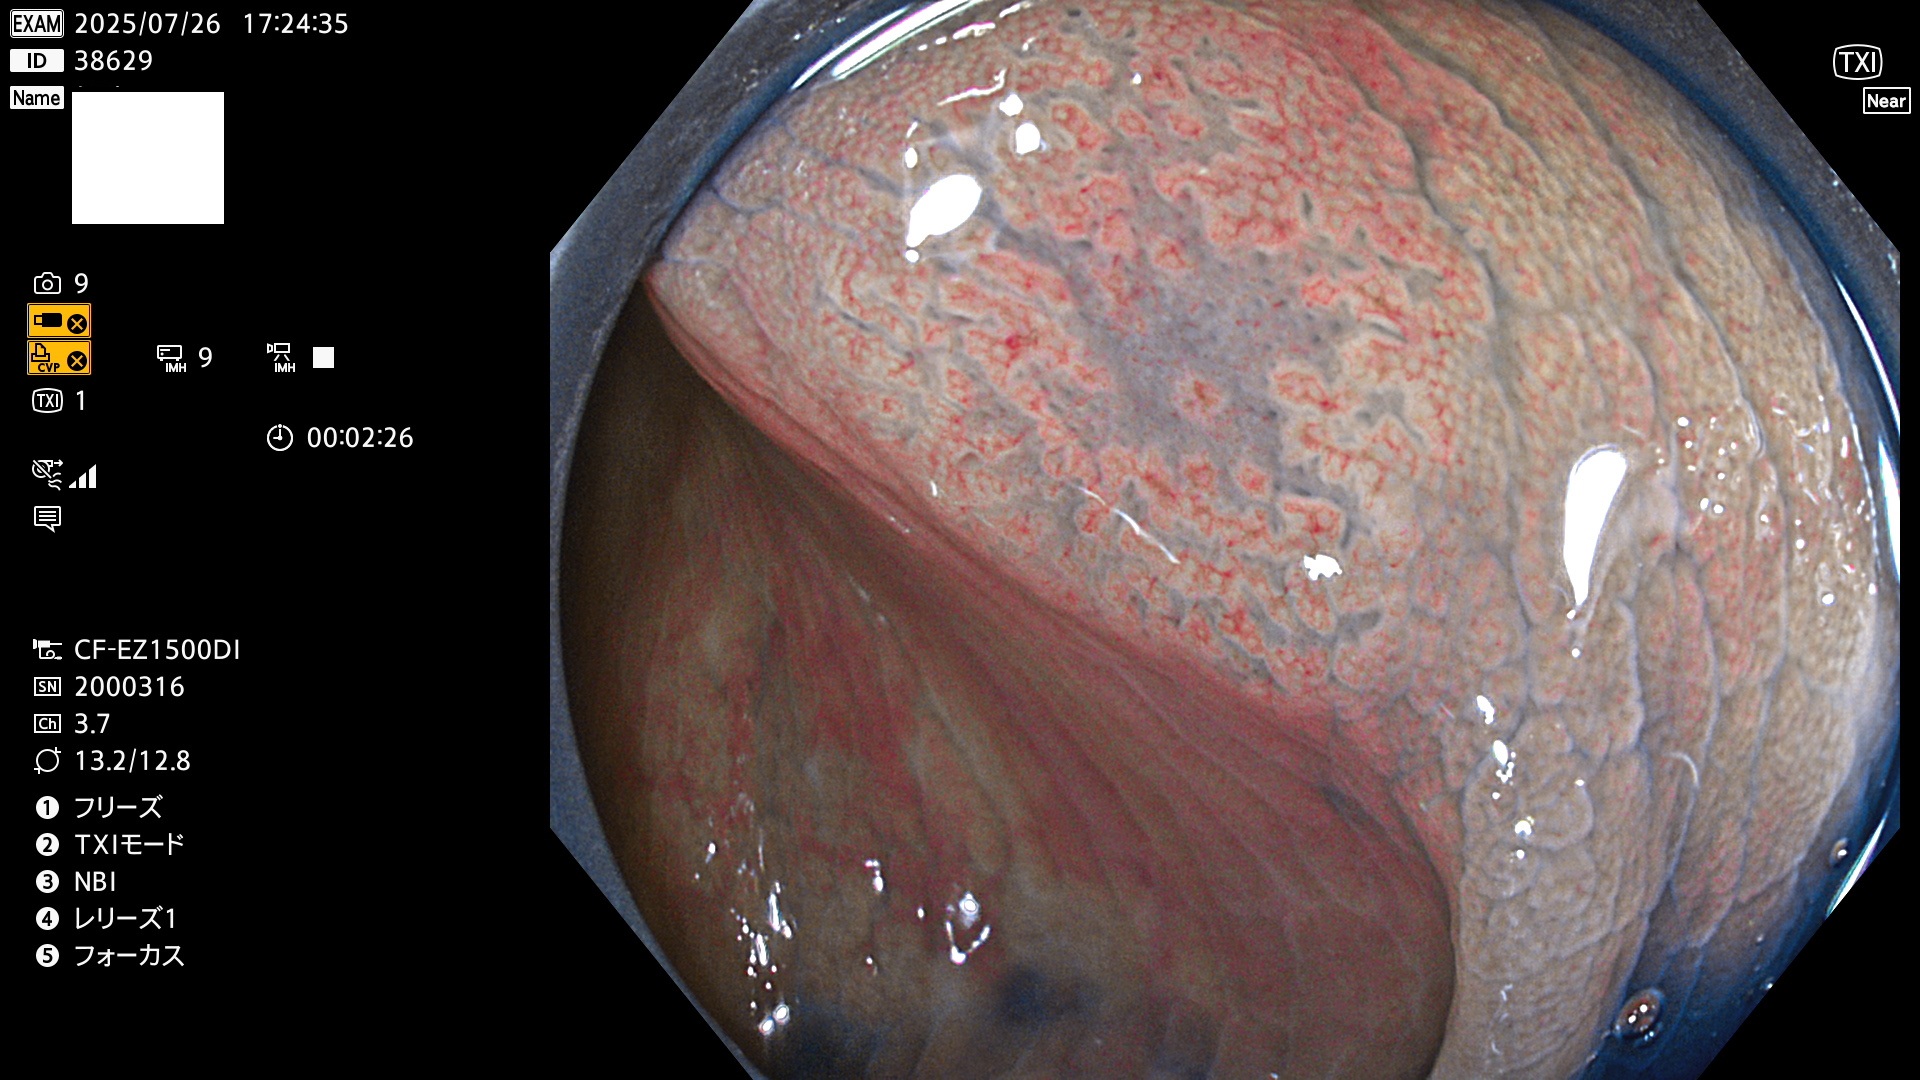

完全に平坦な物をUb、陥凹している物をUcと呼びます。Ubは認識が困難で、Ucはびらん(炎症)と紛らわしいために見落とされやすく、「内視鏡後・大腸癌」の原因になります。

専門的)何故、陥凹していると危険? 癌遺伝子の変異が蓄積すると細胞分裂が盛んになり隆起するのでは?と通常は思われるでしょう。しかし実際は逆です。これは2022年の記事にある「細胞はストレスに直面したら細胞分裂を止める(Dormancy 細胞老化に入り休眠する)という生命の基本的現象」によるものです(Oncogene Stress)。細胞老化を起こすのが癌抑制遺伝子で、この安全装置(ブレーキ)が壊れると癌になります(休眠からの覚醒)。ですから陥凹は「まだ癌では無いが癌化の直前」を意味します。特に「小サイズなのに陥凹している」病変は短期間に腫瘍進化(IntraTumor Heterogenity⇒2021年記事)が起きたことを意味します(=ゲノム不安定性)。

専門的)細胞生物学的Ucの再定義UcをPitと形態学で定義するのは医学的には全く不毛です。Ucの本質はIntraTumor HeterogenityとTumor Dormancyが微小病変に見られる点です。これは早い腫瘍進化=ゲノム不安定性を意味します。そのような病変は隆起型でも形態によらずUcと定義すべきです。なぜなら1年後には陥凹し典型的Uc(最悪の場合NPG癌)になるからです。

2025年7月24日〜7月27日の4日間(40件)15個 (Uc_ADR=15個/40人=38%)